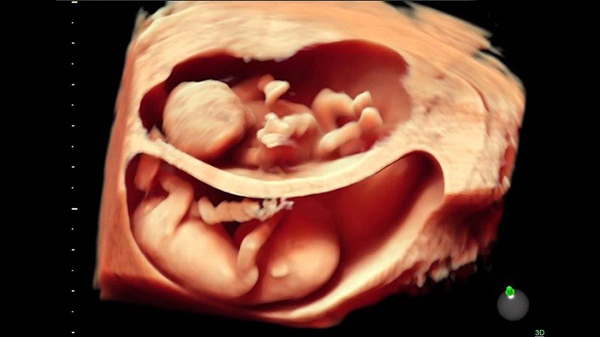

Đường kính lưỡng đỉnh (thông số BPD) là kích thước đo được tại mặt cắt lớn nhất của vùng từ trán ra sau gáy của thai nhi. Một cách đơn giản, đây chính là đường kính phần đầu thai nhi. Phương pháp siêu âm được áp dụng để xác định đường kính lưỡng đỉnh thai.

Siêu âm xác định đường kính lưỡng đỉnh thai

Khi thai bước vào tuần thứ 13 trở đi, mẹ bầu có thể siêu âm để biết các chỉ số đường kính lưỡng đỉnh, chi vi đầu, chiều dài xương,…của thai nhi. Trong suốt thai kỳ, đường kính lưỡng đỉnh thai thay đổi rất nhanh. Đường kính lưỡng đỉnh thai 37 tuần là một chỉ số quan trọng biểu hiện tình trạng thai nhi ở giai đoạn chuẩn bị chào đời.

Đường kính lưỡng đỉnh thai cùng với các chỉ số khác là căn cứ để xác định trọng lượng, tuổi thai và tốc độ phát triển hiện tại của thai nhi. Khi siêu âm và nhận thấy đường kính lưỡng đỉnh không đạt chuẩn, bác sĩ có thể yêu cầu tiến hành các xét nghiệm khác để kiểm tra dấu hiệu bất thường ở thai nhi. Chỉ số đường kính lưỡng đỉnh phải trong một giới hạn nhất định. Nếu đường kính lớn đồng nghĩa với phần đầu của thai lớn sẽ gây khó khăn cho mẹ bầu khi sinh.